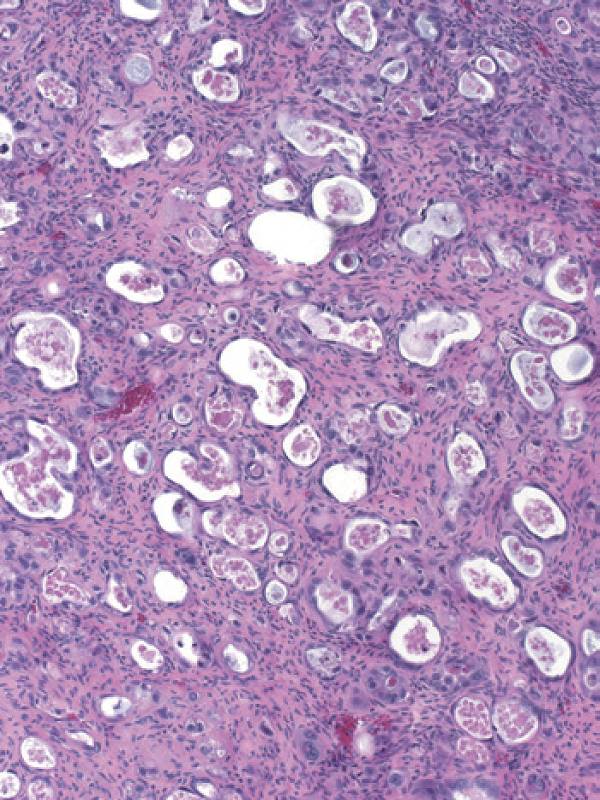

彩图4-2 卵巢透明细胞癌呈现典型管状囊性结构

彩图4-3 卵巢透明细胞癌

乳头状结构中基质玻璃样变是许多透明细胞癌乳头中的典型特征

彩图4-4 典型混合细胞类型卵巢透明细胞癌,少量管状囊性结构(右上)与大量含透明细胞质的细胞结节样生长共存(左下)